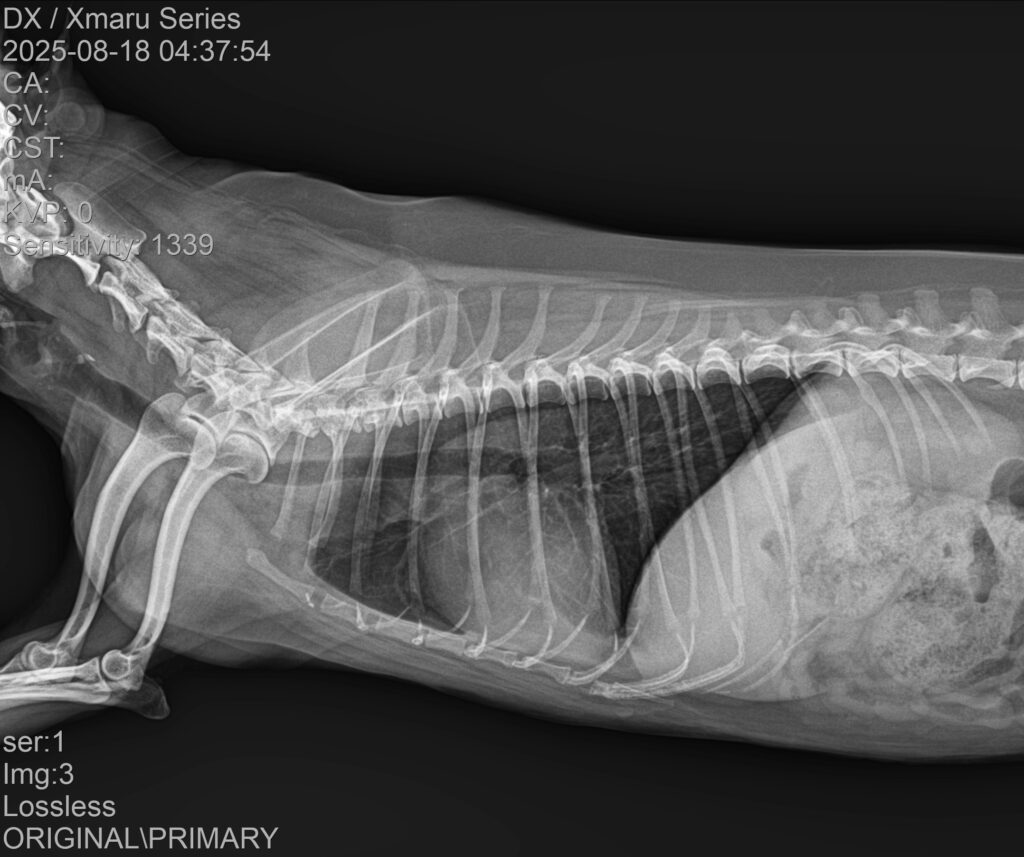

✔ 폐야 침윤 감소

3일차 방사선에서 이미 뚜렷한 호전이 확인되었으며, 7일차 촬영에서는 초기 침윤 부위가 현저하게 줄어든 모습이 관찰되었습니다.

7일차 방사선 사진 / 출처: 강서YD 동물의료센터